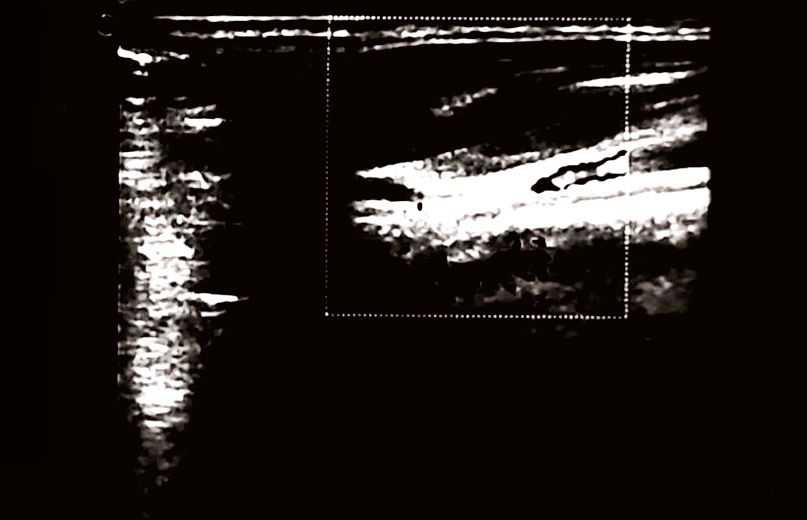

Follow-up Doppler showed progressive improvement. Initial findings are presented in Figure 1: right jugular “bottleneck,” reduced flow; compressible left jugular. By week four, improvement was noted in both, and after eight weeks of treatment (Figure 1(B)) and two additional maintenance sessions, the 16 week-follow-up (Figure 2(A)) venous normalization. By 24 weeks (Figure 2(B)): maintained normalization, stable IMT. Clinically: headache resolved (2 - 3/week to 0); FSS-9 5.6 to 3.1; PSQI 9 to 5; VAS 7 to 2; SCM PPT +45%; cervical mobility +35%. Minor side effects were reported, as mild pain (2/8 initial sessions), resolving haematomas. Maintained improvements at follow-ups, with limited exercise adherence, suggest DN’s primary benefit.

(A)

(B)

Figure 2. (A): After 16 weeks (including 8 weeks of initial treatment and two maintenance Dry Needling sessions), a follow-up examination revealed no significant variation in the carotid arteries compared to previous examinations. The jugular system, however, showed further improvement. The right jugular vein presented with a normal caliber, no signs of a bottleneck, and restored, phasic flow. The left jugular vein maintained good compressibility and adequate flow. These findings confirmed a normalization of extracranial venous circulation, which was sustained even after the conclusion of the intensive treatment phase. (B): After 24 weeks (including initial, and 4 maintenance sessions), the final examination showed an unchanged profile in the carotid arteries. The right jugular vein exhibited normal and phasic flow, with no evidence of residual obstruction. This confirmed that the clinical and hemodynamic improvements were maintained at this timepoint, with no signs of CCSVI recurrence.